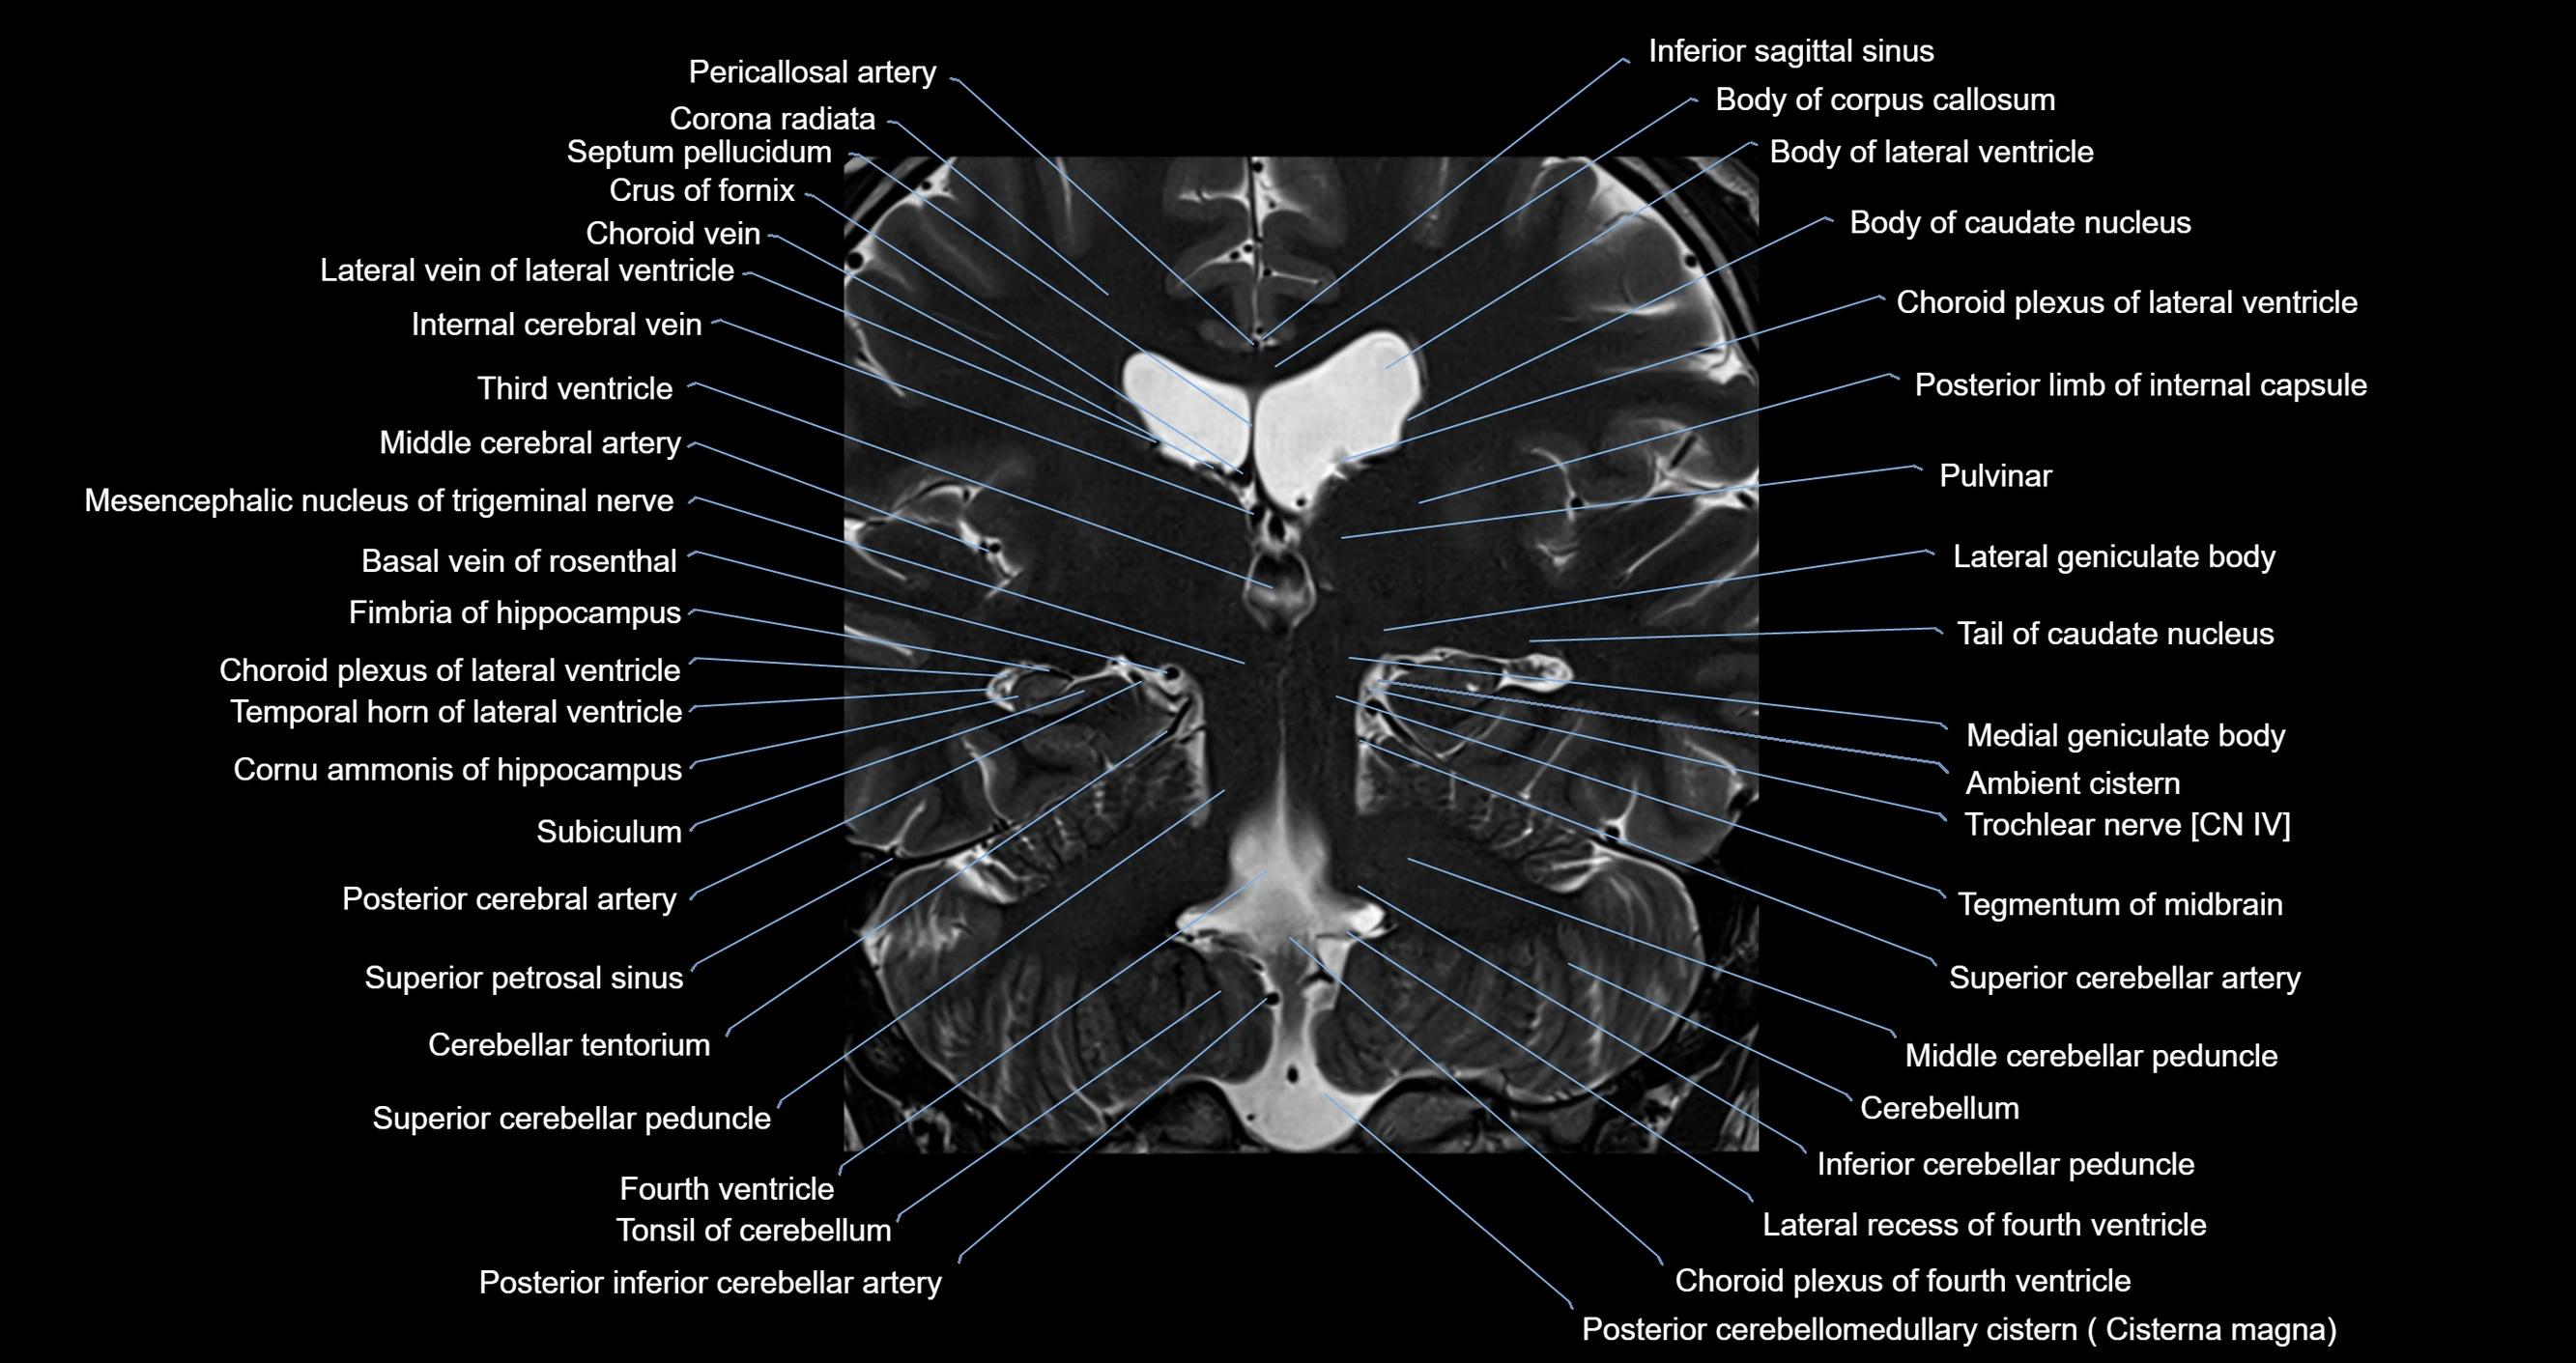

MRI images